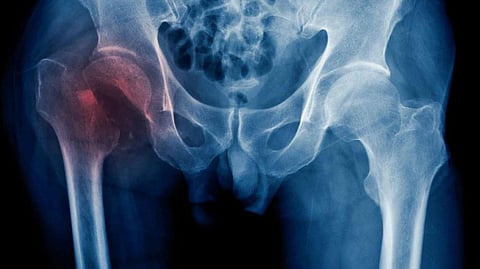

शाकाहारी महिलांमध्ये हिप फ्रॅक्चरचा धोका 33 टक्के, धोका कमी कसा करायचा?

Hip Fracture : एखाद्या व्यक्तीला शाकाहारी असण्याची अनेक कारणे असू शकतात, जसे की पर्यावरणीय किंवा नैतिक कारणे. अनेकांचा असा दावा आहे की शाकाहारी होण्याचे मुख्य कारण म्हणजे त्याचे संभाव्य आरोग्य फायदे. काही पुरावे आहेत की शाकाहारी आहार मधुमेह, हृदयरोग आणि कर्करोगाच्या कमी जोखमीशी संबंधित आहे. पण ही चिंतेची बाब आहे, शाकाहार करणाऱ्यांना हाडांचे आरोग्य खराब होण्याचा आणि फ्रॅक्चरचा धोका जास्त असतो, असे लीड्स विद्यापीठाच्या अभ्यासातून समोर आले आहे. जेम्स वेबस्टर आणि जेनेट केड या शास्त्रज्ञांच्या अभ्यासानुसार, शाकाहारी महिलांना हिप फ्रॅक्चरचा धोका 33% जास्त असतो. (hip fracture risk vegetarian women on 33 percent higher risk study revealed)

The Conversation मध्ये नोंदवल्याप्रमाणे, पूर्वीच्या अभ्यासातून असे दिसून आले आहे की शाकाहारी लोकांमध्ये हाडांची खनिज घनता कमी असते. परंतु शाकाहारी लोकांना विशिष्ट प्रकारच्या फ्रॅक्चरचा धोका जास्त असतो की नाही हे फारच कमी संशोधनाने ठरवले आहे-विशेषतः हिप फ्रॅक्चर. हा फ्रॅक्चरच्या सर्वात सामान्य प्रकारांपैकी एक आहे आणि याचा स्त्रियांवर विषम परिणाम होतो.

अभ्यासानुसार, जे नियमितपणे आठवड्यातून 5 वेळा मांस खातात त्यांच्यापेक्षा शाकाहारी लोकांना हिप फ्रॅक्चरचा धोका जास्त असतो. मांसाहार करणाऱ्यांमध्ये किंवा अधूनमधून मांस खाणाऱ्यांमध्ये कोणताही धोका वाढलेला नाही. या अभ्यासाचे निष्कर्ष मुख्यत्वे या विषयावरील इतर दोन अभ्यासांच्या निकालांशी सहमत आहेत. 2020 च्या एका अभ्यासात असे दिसून आले आहे की, मांसाहार करणार्यांपेक्षा शाकाहारी लोकांना (स्त्री आणि पुरुष दोन्ही) हिप फ्रॅक्चरचा धोका 25% जास्त आहे. त्याचप्रमाणे, 2021 मधील यूएस अभ्यासात असे दिसून आले आहे की शाकाहारी लोकांमध्ये मांसाहारी लोकांपेक्षा हिप फ्रॅक्चरचा धोका 17% जास्त आहे.